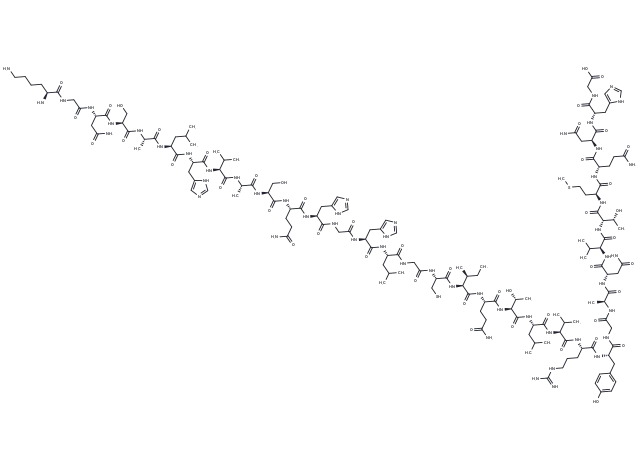

– [C@@H](CC1=CN=CN1)(NC([C@@H](NC([C@@H](NC([C@@H](NC([C@@H](NC(CNC([C@H](CCCCN)N)=O)=O)CC(N)=O)=O)CO)=O)C)=O)CC(C)C)=O)C(N[C@H](C(N[C@H](C(N[C@H](C(N[C@H](C(N[C@@H](CC2=CN=CN2)C(NCC(N[C@@H](CC3=CN=CN3)C(N[C@H](C(NCC(N[C@H](C(N[C@H](C(N[C@H](C(N[C@H](C(N[C@H](C(N[C@H](C(N[C@H](C(N[C@@H](CC4=CC=C(O)C=C4)C(NCC(N[C@H](C(N[C@H](C(N[C@H](C(N[C@H](C(N[C@H](C(N[C@H](C(N[C@H](C(N[C@@H](CC5=CN=CN5)C(NCC(O)=O)=O)=O)CC(N)=O)=O)CCC(N)=O)=O)CCSC)=O)[C@@H](C)O)=O)C(C)C)=O)CC(N)=O)=O)C)=O)=O)=O)CCCNC(=N)N)=O)C(C)C)=O)CC(C)C)=O)[C@@H](C)O)=O)CCC(N)=O)=O)[C@H](CC)C)=O)CS)=O)=O)CC(C)C)=O)=O)=O)=O)CCC(N)=O)=O)CO)=O)C)=O)C(C)C)=O